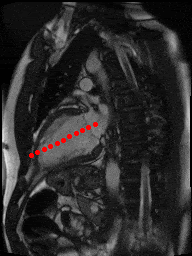

Another interesting project we did involved automatic stomatological assessment. We trained a model to read an x-ray image and detect and identify teeth, accessories and lesions including laces, implants, cavities, cavity fillings, and parodontosis, among a long list of others. In yet another project, we estimated minimum (end-systolic) and maximum (end-diastolic) volumes of the left ventricle from a set of MRI-images taken over one heartbeat. Our results were rated “excellent” by cardiologists that reviewed our work.